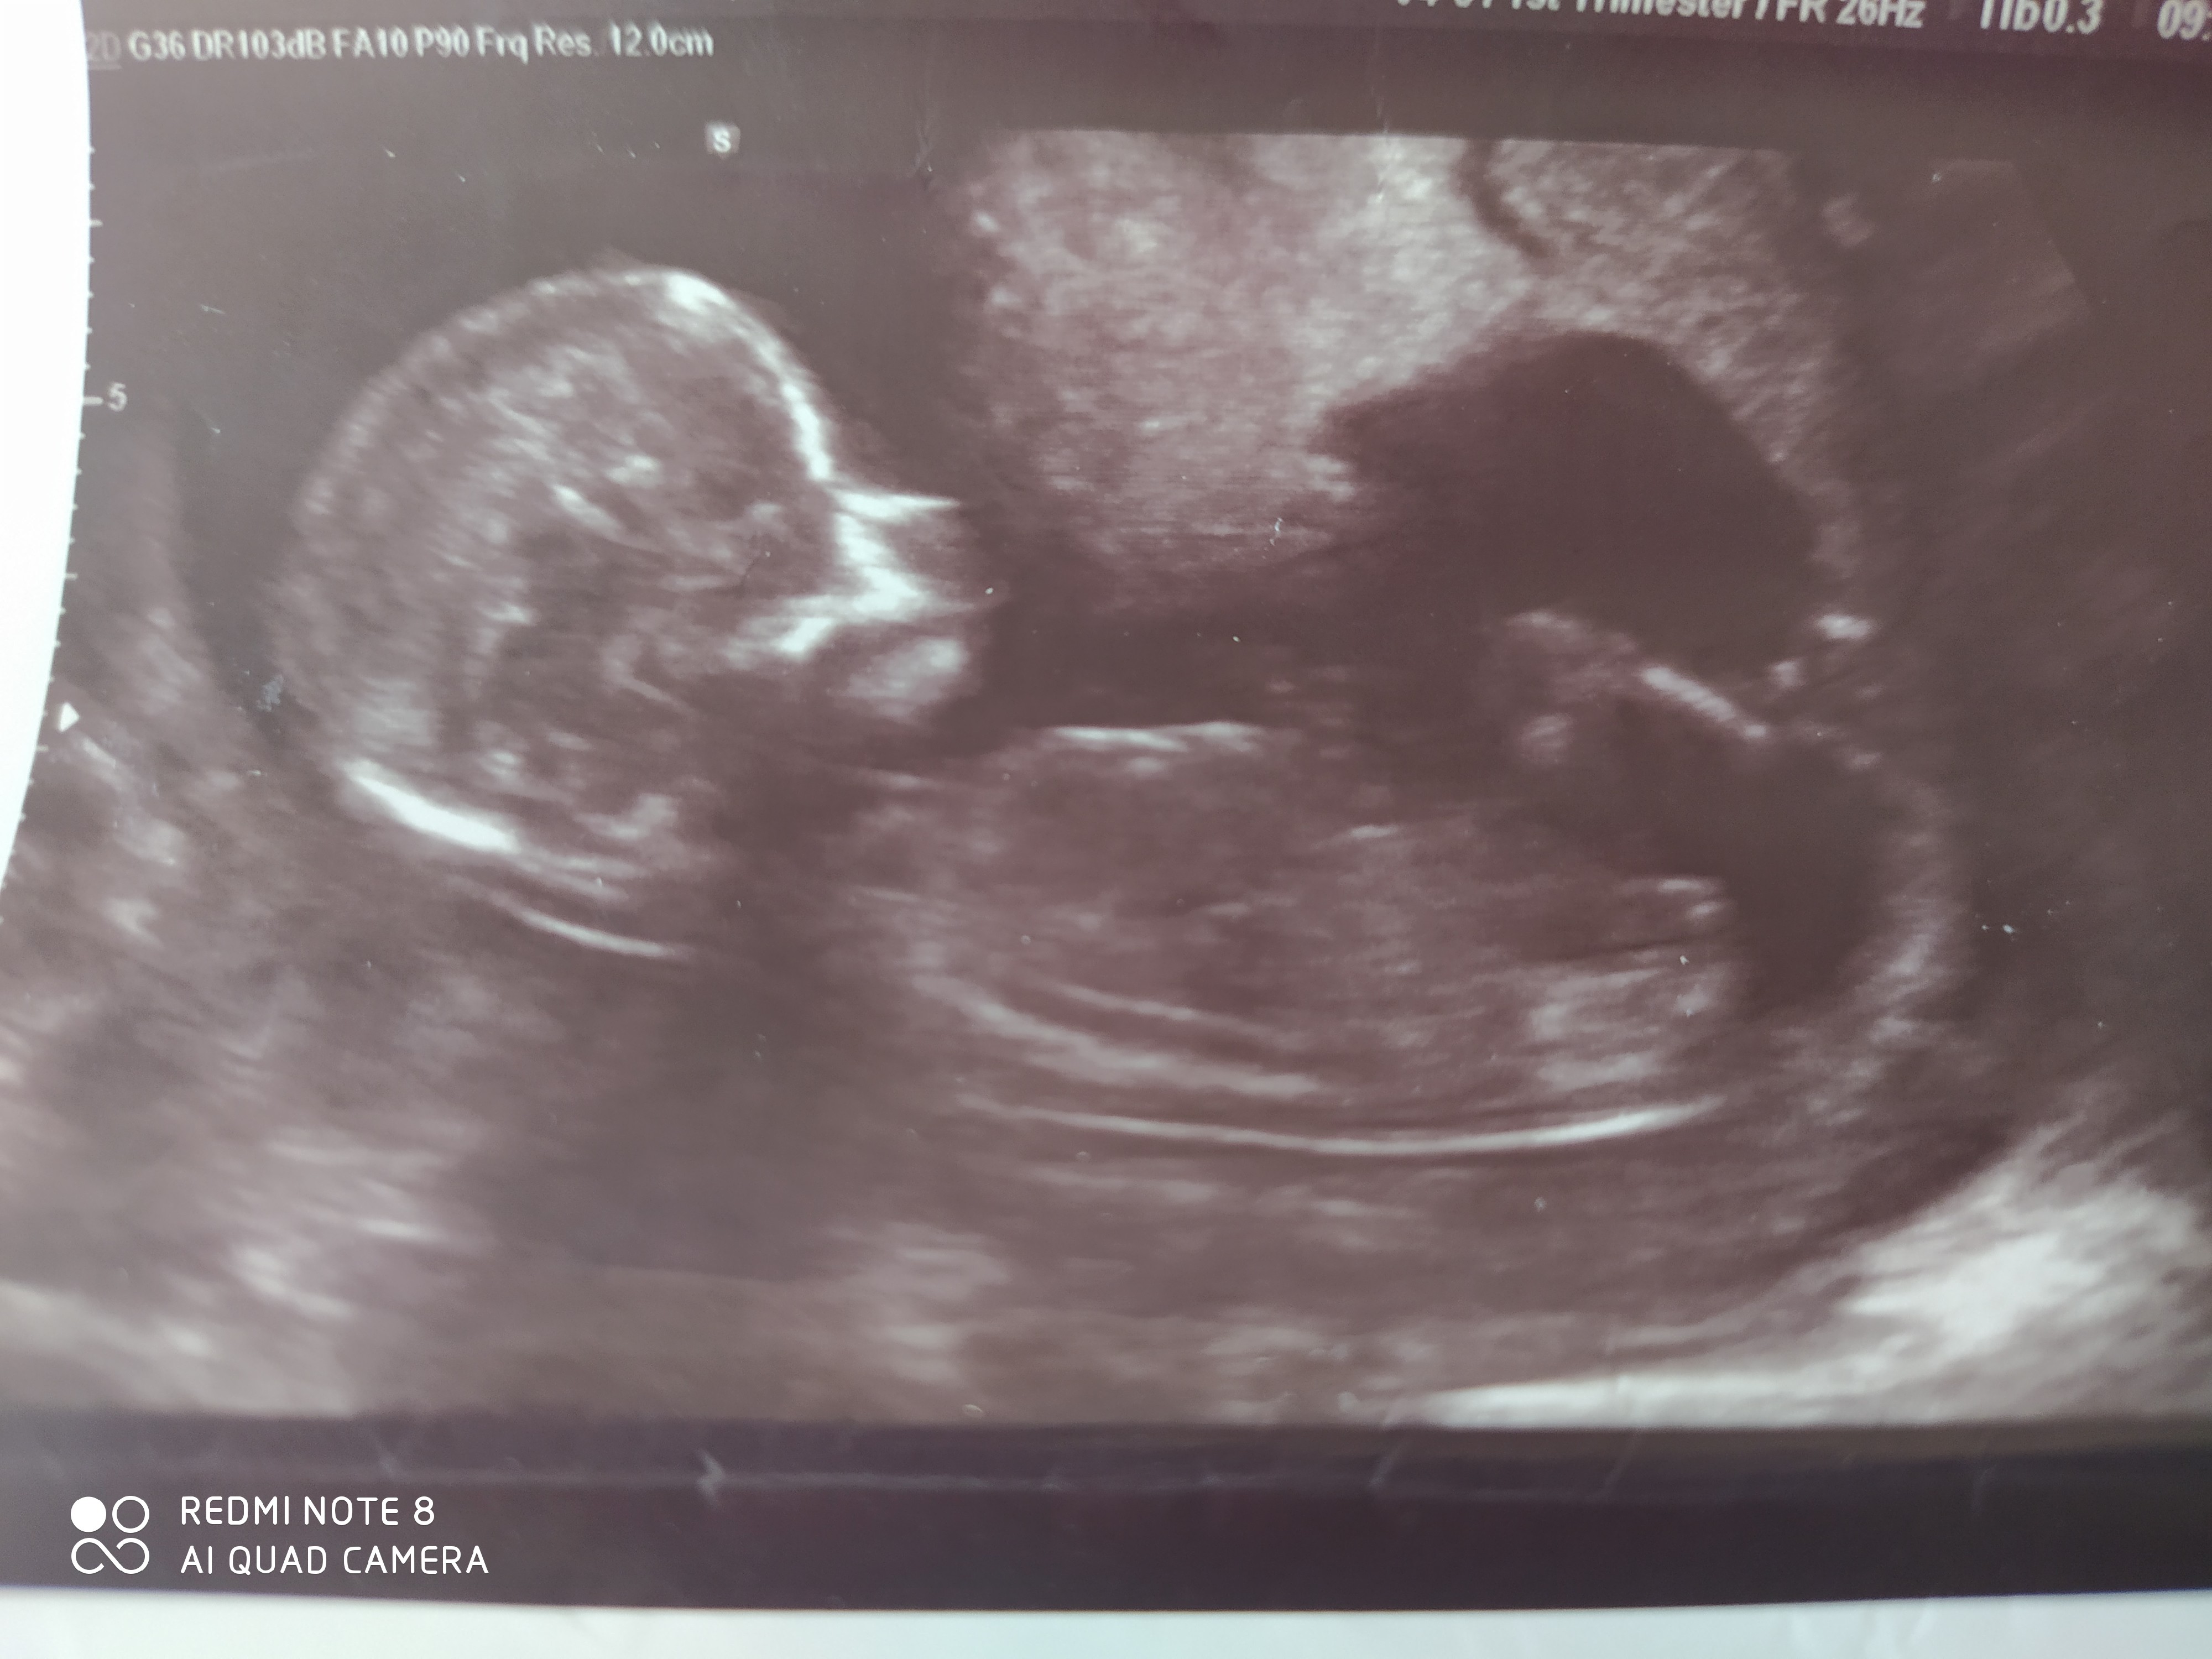

Witam serdecznie🙂 Byłam ostatnio na badaniach prenatalnych i dowiedziałam się, że będzie dziewczynka 14+2 TC ,a wcześniej w 13 TC byłam na zwykłym USG i lekarz obstawiał chłopca... może byście zerknęły na zdjęcia i dały znać kto mnie zamieszkuje..z góry bardzo dziękuję za pomoc i pozdrawiam 🙂

• IMG_20200313_081136.jpg

IMG_20200313_081136.jpg

1,2 MB · Wyświetleń: 245

Dzoecko jest bokiem, nie da się nic zobaczyć 😉 ale skoro na prenatalnych tak powiedzieli, to bym się tego trzymała

Hmmm ginekolog na podstawie tych zdjęć stwierdzała 😉..na fb jest też taka strona nub gender i na podstawie tego odstającego wyrostka potrafią ocenić tylko, że ja nie bardzo się w tym orientuję 🙂

Przez ostatni tydzień już się oswajałam z wiadomością o chłopczyku,a teraz na prenatalnych ginekolog zaskoczyła nas tą dziewczynką, gdy jej wspomniałam, że tydzień wcześniej byl chłopiec to zaczęła wnikliwie oglądać, powiększać i stwierdziła, że nic nie odstaje i niby między nogami nie ma.. płeć nie jest dla nas najważniejsza, choć nie powiem, że nadzieja o dziewczynce bardzo nas ucieszyła, gdyż synka już mamy ☺️ pozdrawiam 😉

Hey @AśkaW89 :) choć z 14tc już się nie patrzy na nuba... (teraz jak będziesz po 16tc to niech robi potty shot i już będzie coś widać ;) ) to powiem Ci że mnie wyglada również na dziewczynkę